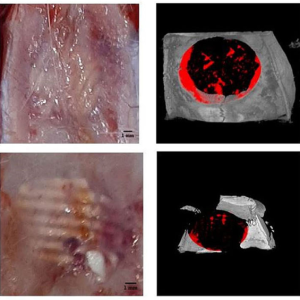

بازسازی نقایص استخوانی در مدل استئونکروز فمور خرگوش با استفاده از داربستهای کامپوزیت پلی (اپسیلون-کاپرولاکتون)/نانوذرات ویلمایت

نویسندگان: لطیفه کریمزاده باردیی، احسان سیدجعفری، قمرتاج حسین، محمد نبیونی، محمد حسین مجلس آرا و Jochen Salber چکیده:استئونکروز مرتبط با استروئید (SAON)[1] یک بیماری مزمن است